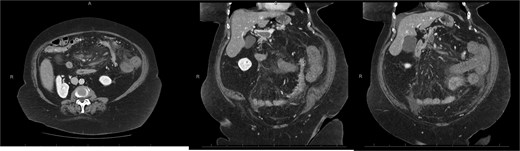

A 76-year-old female with a 3-day history of left upper abdominal pain, vomiting, and haematochezia. Her history included pulmonary embolism, multiple deep vein thromboses, with no ongoing anticoagulation, and an open partial colectomy for complicated diverticulitis a decade earlier. On admission, she was afebrile but tachycardic and showed localized tenderness in the left hypochondrium. Laboratory revealed leucocytosis with a white blood cell count (WBC) of 12 G/L, elevated C-reactive protein (CRP) of 46 mg/L, and hyperlactatemia of 2.6 mmol/l. Enhanced computed tomography (E-CT) revealed jejunal venous ischemia in the left upper quadrant, secondary to extensive porto-mesenteric thrombosis with reduced bowel wall enhancement, distention, and free intraperitoneal fluid (Fig. 1). She was managed conservatively with unfractionated heparin (UFH) with a bolus of 5000 U/l followed by 30 000 U/l/24 h (target INR 0.35–0.7), Piperacillin-Tazobactam, and bowel rest. After 48 h of monitoring in the intensive care unit (ICU), she exhibited marked biological and clinical improvement. E-CT on the third day showed restored bowel wall enhancement and stable porto-mesenteric thrombosis (Fig. 2). She was discharged on therapeutic low molecular weight heparin (LMWH) with enoxaparin sodium 120 mg every 12 h. At the 3-month follow-up, E-CT revealed near-complete thrombus resolution, without intestinal sequelae (Fig. 3).

Three-month E-CT of the first patient showing nearly complete thrombosis resolution, with no signs of intestinal distress.